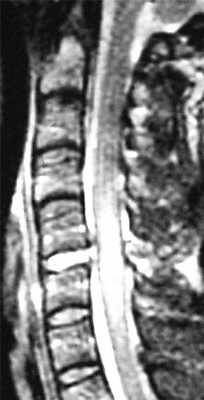

(Справа) На сагиттальном STIR МР-И отмечается отек костного мозга, связанный с переломами С7 и Т1 позвонков, и выраженный отек превертебральных мягких тканей. В заднем отделе эпидурального пространства видна гематома, умеренно сдавливающая спинной мозг. Признаков кровоизлияния в вещество спинного мозга нет. (Слева) КТ-ангиограмма: типичные признаки тяжелого гиперфлексионного повреждения шейного отдела позвоночника в виде подвывиха С5 с переломом кранио-вентрального угла тела С6 и значительным расширением межостистого промежутка, отражающим разрыв межостистых связок.

МРТ шейного отдела позвоночника. Острая травма. Компрессия спинного мозга, отек и контузия. Сагиттальная Т2-взвешенная МРТ.

МРТ шейного отдела позвоночника. Т2-взвешенная сагитальная МРТ. Острая травма с повреждением задних элементов позвонков и отеком спинного мозга.

МРТ шейного отдела позвоночника. Острая травма. Отёк спинного мозга. Сагиттальная Т2-взвешенная МРТ.